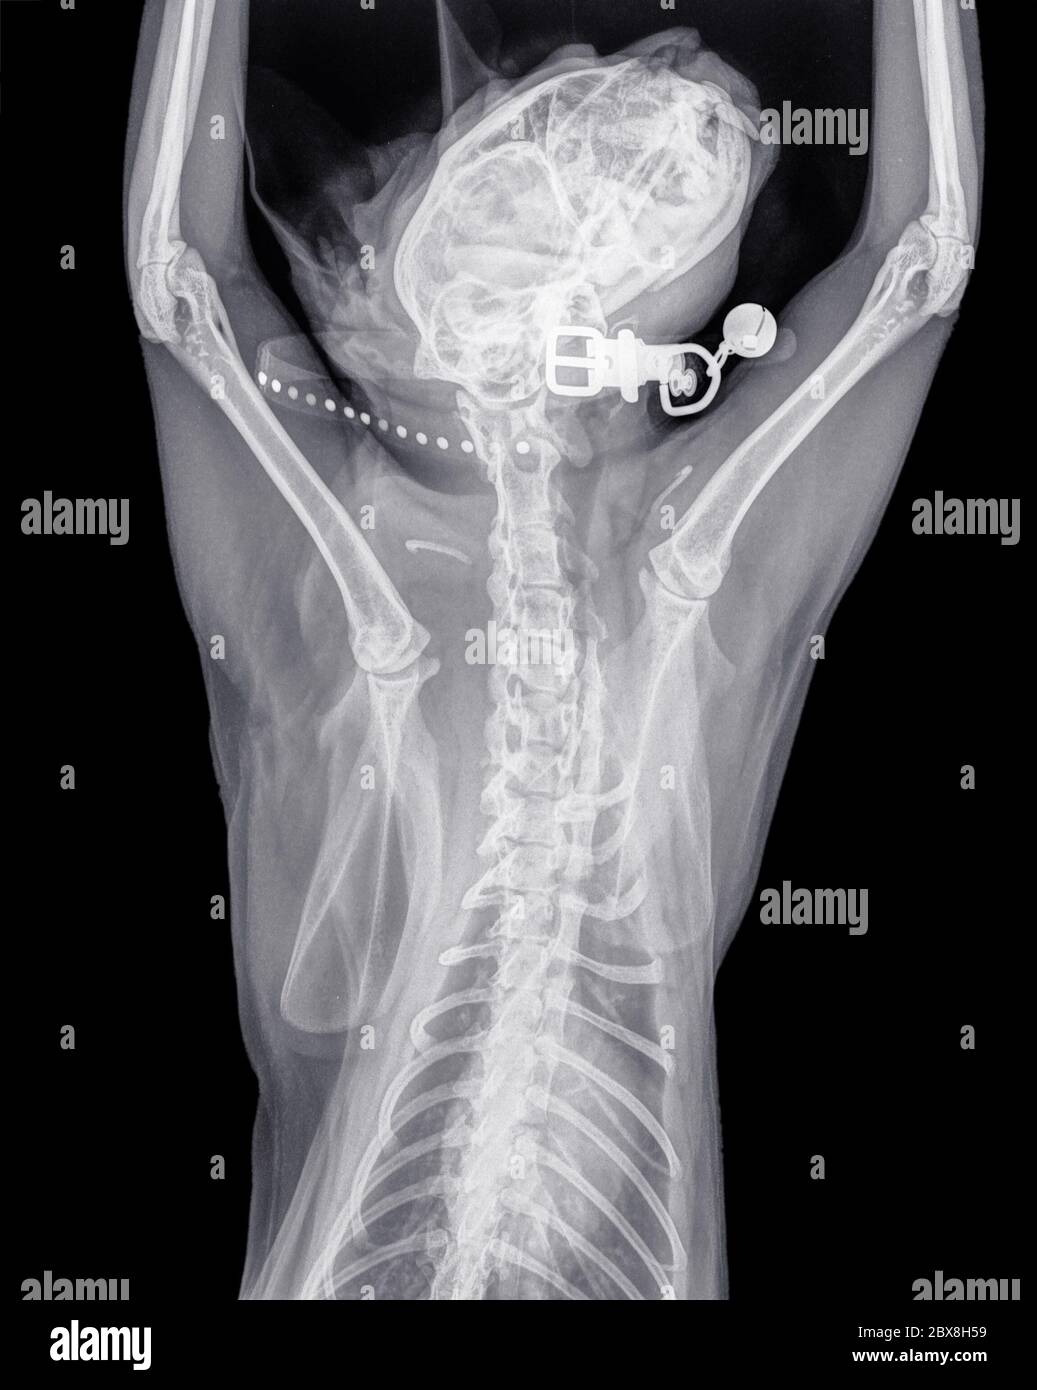

Cat Neck X Ray . Cat that was shot in the neck with a pellet. Did you see the microchip on this view (black arrow)? You will be given examples of normal ones, and a given a chance to make a diagnosis on abnormal ones. Wires in a fractured mandible (lower jaw) foreign body in the stomach.

You will be given examples of normal ones, and a given a chance to make a diagnosis on abnormal ones. Wires in a fractured mandible (lower jaw) foreign body in the stomach. Cat that was shot in the neck with a pellet. Did you see the microchip on this view (black arrow)?